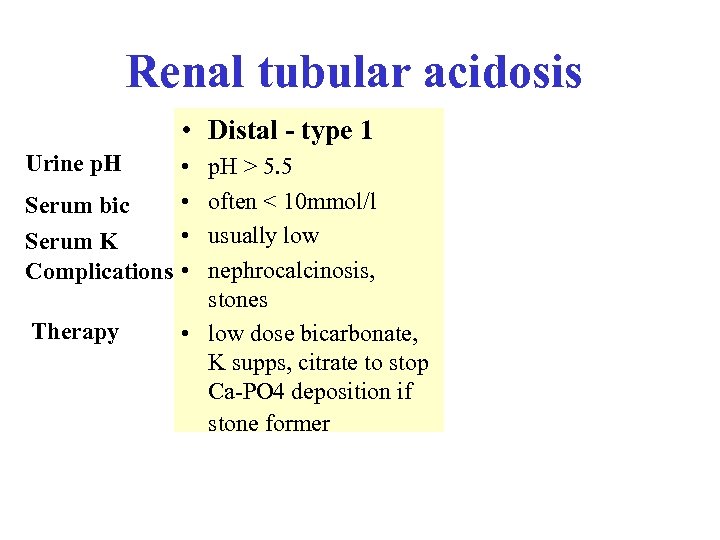

Renal tubular acidosis • Distal - type 1 Urine p. H • • Serum bic • Serum K Complications • Therapy p. H > 5. 5 often < 10 mmol/l usually low nephrocalcinosis, stones • low dose bicarbonate, K supps, citrate to stop Ca-PO 4 deposition if stone former

Renal tubular acidosis • Distal - type 1 Urine p. H • • Serum bic • Serum K Complications • Therapy p. H > 5. 5 often < 10 mmol/l usually low nephrocalcinosis, stones • low dose bicarbonate, K supps, citrate to stop Ca-PO 4 deposition if stone former

Renal tubular acidosis • Distal - type 1 Urine p. H • • Serum bic • Serum K Complications • Therapy • Proximal - type 2 p. H > 5. 5 • often < 10 mmol/l • usually low • nephrocalcinosis, • stones • low dose bicarbonate, • K supps, citrate to stop Ca-PO 4 deposition if stone former Variable* 14 -20 mmol/l* normal or low osteomalacia, rickets (not calcinosis or stones) high dose bicarbonate *when serum bicarb drops below a threshold level in type 2 RTA, the tubules start reabsorbing bicarbonate which means serum bic can be higher and urine p. H lower than in type 1 - known as the “threshold effect”